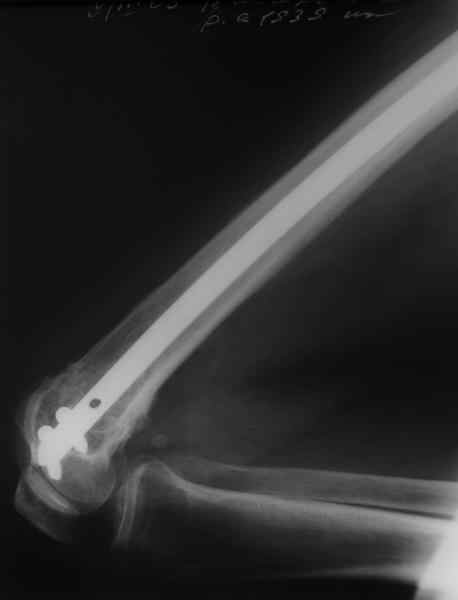

Результат операции блокирующего остеосинтеза многооскольчатого перелома бедра. Применены винты собственной конструкции.(моделирование спогиозного винта)

По прямой проекции неплохо. Что за стержень?

Примеры приложены.

Алекс, как Вы можете говорить, что "по прямой проекции неплохо"!? :( Гвоздь в суставе !!!

Снимаю свои претензии. На втором из снимков, которыми Вы хвастаетесь, гвоздь тоже в суставе, и ничего :(

И какие страшные проблемы от этого тянут аж на три восклицательных знака?

Если даже будет patellar impingement, это решается удалением после сращения.

И вообще мне кажется, что представленный ОС не допустим:1. стержень в суставе,2. неправильная длинна винтов, 3. ось конечности неправильная, 4. циркулярная гипсовая повязка после ОС?????

-1. стержень в суставе,

Это не критично, в межмышелковой борозде,не на опроной поверхности, выступает из субхондральной кости, не факт что из хряща.Про надколенник Александр Николаевич уже писал.

Вполне прилично. Если в боковой проекции рекувации нет. Где кстати боковая, хочется спросить у постмейкера.

Приносим извенения за недостаток информации. Выкладываю все снимки. Стержень фирмы НПО ДЕОСТ(г.Пущино-на-оке)

Чтобы больной не смог сгибать колено, выстоять в сустав железо должно побольше значительно, чем на 1 мм. В приложении снимок с выстоянием ммм на 3, видна и функция колена. Хотя клиника импинджмента была, но даже не на один восклицательный знак. После удаления стержня проблемы и вовсе рассосались.

Это результат через полгода. К сожалению, пациент больше не приезжал на контрольный осмотр.